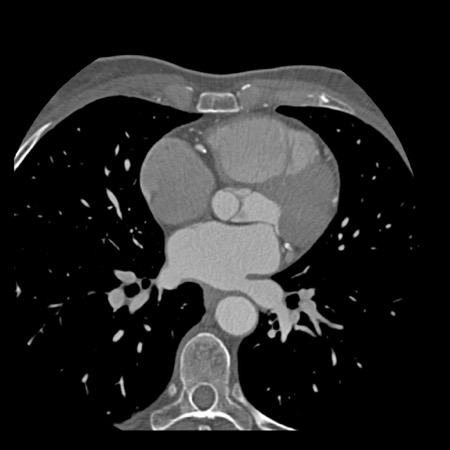

Modifier S – stent

The presence of a stent is indicated by modifier “S”.

Examples

- If a patient has a stent, showing no in-stent restenosis and a mild

(25-49%) stenosis in the coronaries, this patient classifies as CAD-RADS

2/S. - Similarly, a patient with no in-stent restenosis but severe (70-99%)

stenosis in a coronary other than LM classifies as CAD-RADS 4A/S. - If there is a severe (70-99%) in-stent restenosis in a coronary other

than LM, this patient classifies as CAD-RADS 4A/S. - If the stent is non-diagnostic and there is no >49% stenosis present

in the coronaries, the patient classifies as CAD-RADS N/S.

Note: the location of the stenosis does not matter, when using

CAD-RADS.

What matters is that the patient has a severe stenosis and needs further

management.

Please note: total coronary plaque burden should also be added and is

placed before the modifier S.